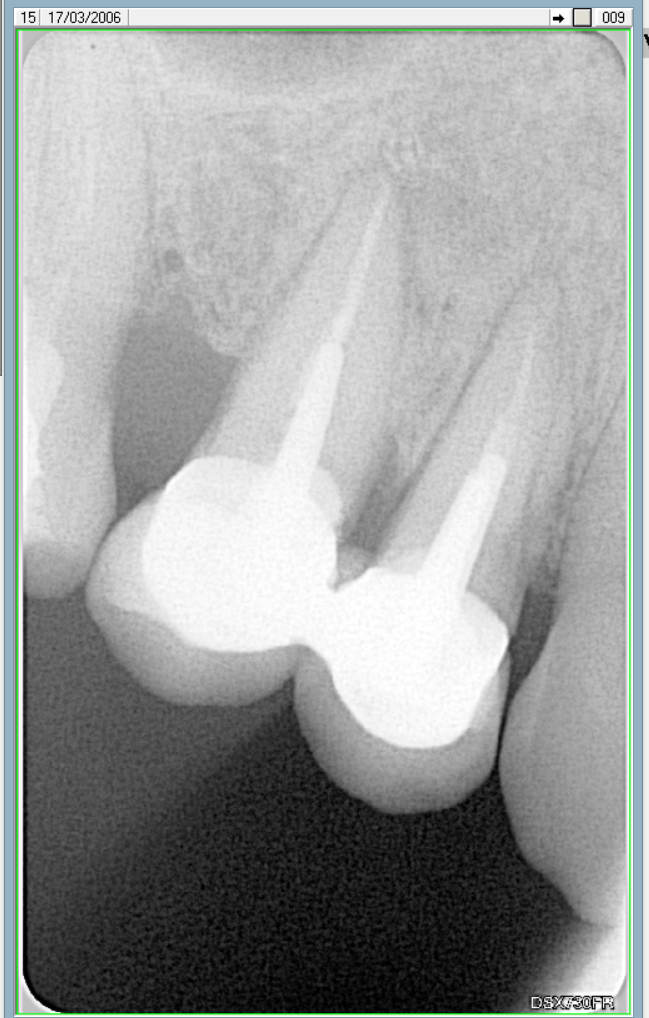

Femme de 71 ans................4 et 2 ans de recul ( les numéros de dents sont faux )

Capture d écran 2017 03 21 à 12.15 - Eugenol

Joli ! Mes respects c'est du beau travail.

Mais les lésions ne sont pas similaires à celles nous concernant, on a des paroies restantes même sur la seconde on peut le deviner rien que par la paroi mésiale et une apparence moins radoiclaire au niveau de la racine distale.

Celle-ci en effet pouvaient être sauvées (quoique j'aurai hésité sur la seconde mais pas la première de 2017).

Je ne mangerai donc pas mon davier pour cette fois. Mais encore une fois très beau travail !

regardes bien , sur ce cas , l'endo est pipée avant , elle est pipée après , hein.

je n'ai pas touché l'endo mouhahahazzzz .

y a rien là ????

ç est contrariant ,non ? :-)))))